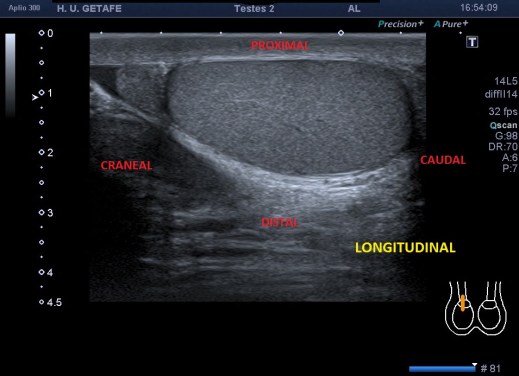

En longitudinal haremos la medida cráneo-caudal y en transverso haremos medidas antero-poterior y derecha izquierda.

Tanto en un plano como en el otro debemos escoger la parte central de la estructura para que las medidas sean fiables.

Corte Longitudinal y medida.Obsérvese el picto.

Rotaremos 90º la sonda hacia la derecha del paciente y encontraremos el corte transverso, buscando la parte central de la estructura y su hilio, por donde se nutre el teste, que lo reconocemos por una imagen hiperecogénica y lateral en el Teste.Ese lugar es idóneo para realizar las otras dos medidas mencionadas previamente.

Corte transverso y medidas laterales y antero-posterior.

En esta imagen del testículo, el epidídimo que se ve, isoecogénico sobre el teste derecho, aparecería en la región caudal, pudiendo llevar a error si la sonda estuviese mal posicionada en el corte longitudinal (observa el pictograma).